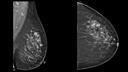

Multifocal intraductal Carcinoma (IDC) and Papillomatosis

A 41-year-old female patient with a palpable lump in the left breast. TiCEM shows very good correlation with MRI and was even better than DBT in the preoperative assessment of breast cancer.

Courtesy of Prof. Luis Pina, MD, University of Navarra, Pamplona/Spain.